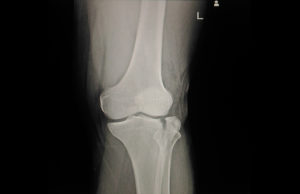

BILAN IMAGERIE

Le bilan radiographique comporte des clichés de face et de profil.

Le scanner est indiqué parfois pour étudier des fractures complexes ou lorsque l’on suspecte des lésions associées et non visibles à la radiographie. le scanner sera utile pour la reconstruction chirurgicale.